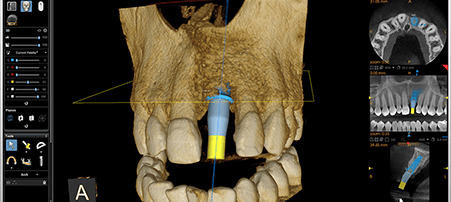

CBCT 3D Scanner

A state of the art scanning machine used to produce incredibly accurate and detailed 3D images. From single teeth to both upper and lower jaws in a single scan with a reduced radiation dose and high speed.

Extremely beneficial in detecting and diagnosing oral health problems and as an aid to planning of treatment. CBCT 3D Scanners are becoming extremely important as dentistry moves further into the digital generation.

- Dental Implant Planning and Placement